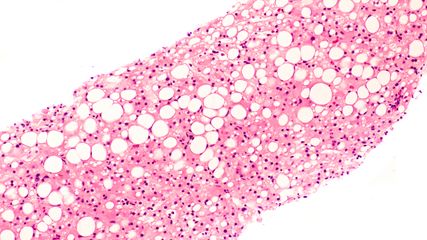

Die portale Hypertension beschreibt einen erhöhten Druck in der Pfortader, also jenem Blutgefäß, welches Blut aus Darm und Milz zur Leber führt.7 Pathophysiologisch liegen der Entstehung der portalen Hypertension strukturelle und funktionelle Veränderungen innerhalb des Leberparenchyms zugrunde, welche den Gefäßwiderstand innerhalb der Leber erhöhen und den Blutfluss somit behindern.7

Zwar kann die portale Hypertension durch die Gabe von Betablockern medikamentös verbessert werden,4 jedoch liegen auch Daten vor, die den positiven Effekt lang anhaltender Alkoholabstinenz bei Patient:innen mit alkoholbedingter Leberzirrhose aufzeigen. Erste Berichte, welche bereits 1960 von Reynolds TB et al.10 veröffentlicht wurden, zeigten beispielsweise eine Verbesserung der invasiv gemessenen portalen Hypertension bei Patient:innen, die durch Alkoholabstinenz eine Rückbildung von Aszites und Ikterus erreicht hatten. Ähnlich zeigte auch eine Studie von Vorobioff J et al.11 im Jahr 1996 einen Rückgang des HVPG bei Patient:innen mit alkoholbedingter Leberzirrhose und Abstinenz. Wie sich die portale Hypertension jedoch nach hepatischer Rekompensation entwickelt, wurde bisher nicht gezielt untersucht, und ob sich CSPH zurückbilden kann, bleibt unklar.